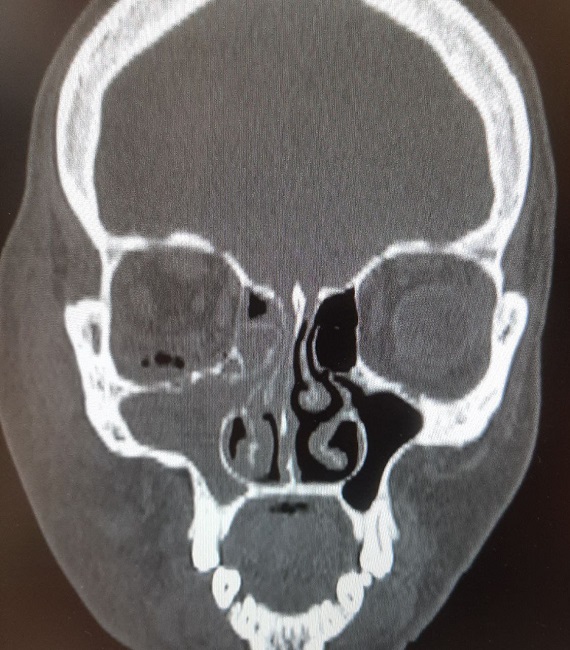

Орловчанке диагностировали флегмому (гнойное воспаление), а также гайморит. При этом площадь инфильтрата (скопления посторонней жидкости) составила 20 на 18 сантиметров. В глазнице образовался газ.

Воспаление возникло на фоне вовремя не ликвидированных стоматологических проблем. Женщина попала в стационар после того, как около 2 недель пыталась решить проблему самостоятельно.

В итоге она дошла до такого состояния, что даже не могла открыть правый глаз. Однако орловчанка рисковала потерять не только часть зрения, но и саму жизнь.